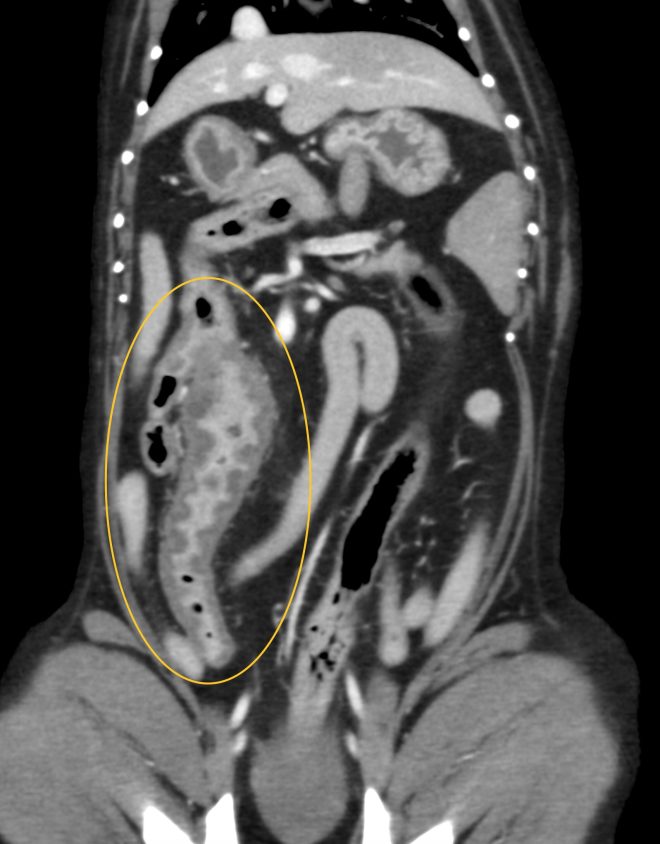

超音波検査を行ったところ、回腸から盲腸、結腸にかけて腸の肥厚と構造の破壊が認められました。腫瘍の可能性も考慮されたため、CT検査と手術(回盲部切除)を行いました。

病理組織学的検査では、リンパ液漏出に伴う肉芽腫性腸炎と診断されました。今後は、食事管理、内科治療が継続的に必要で、再発にも注意が必要です。